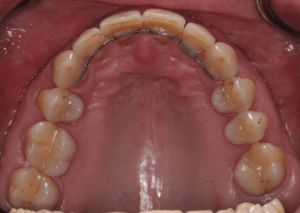

Искривление окклюзионной кривой (плоскости смыкания зубов), возникшее в результате парадонтита, успешно удалось устранить, используя накусочные брекеты на верхних резцах и микроимплант, установленный во фронтальном участке нижней челюсти:

Пациентка довольна профилем и красивой улыбкой.